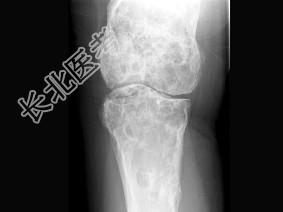

- 单项选择题女,42岁, 双下肢疼痛,结合图像, 最可能的诊断是 ( )

A、Paget病

B、内生软骨瘤

C、非骨化性纤维瘤

D、骨巨细胞瘤

E、骨纤维异常增殖症